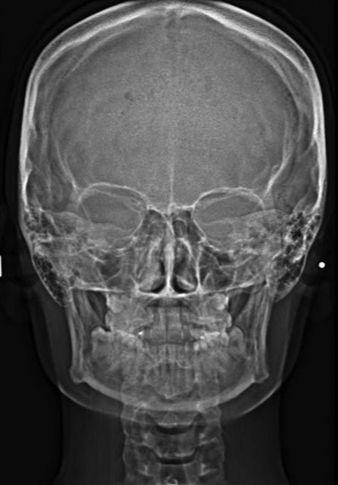

Radiografía postero anterior de cráneo

Técnica radiográfica utilizada para evaluar asimetrías, traumatismos y patologías craneofaciales.